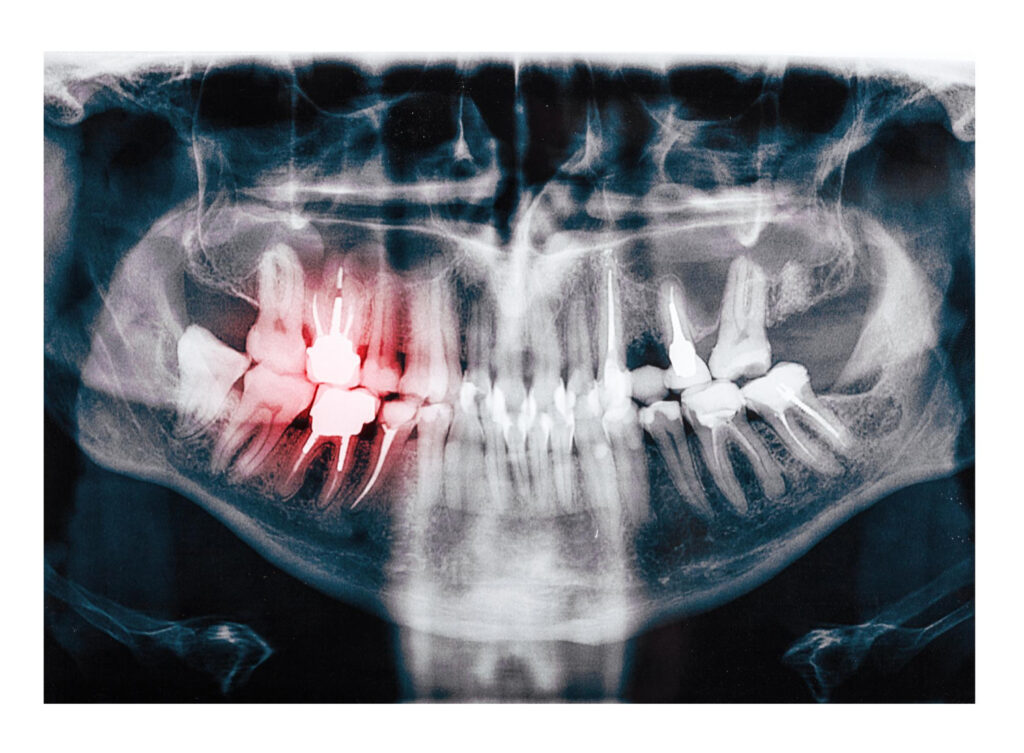

At Scottsdale Dental Solutions, we prioritize your oral health. Our dentists utilize X-rays to examine your teeth, and supporting structures. These images help our clinicians in detecting cavities, missing teeth, abnormal growth, bone damage, cysts, tumors, etc.

These images play a crucial role in identifying various issues, including cavities, impacted teeth, missing teeth, abnormal growth, bone damage, cysts, tumors, etc. The information provided by X-rays is crucial for planning treatments for dental issues.